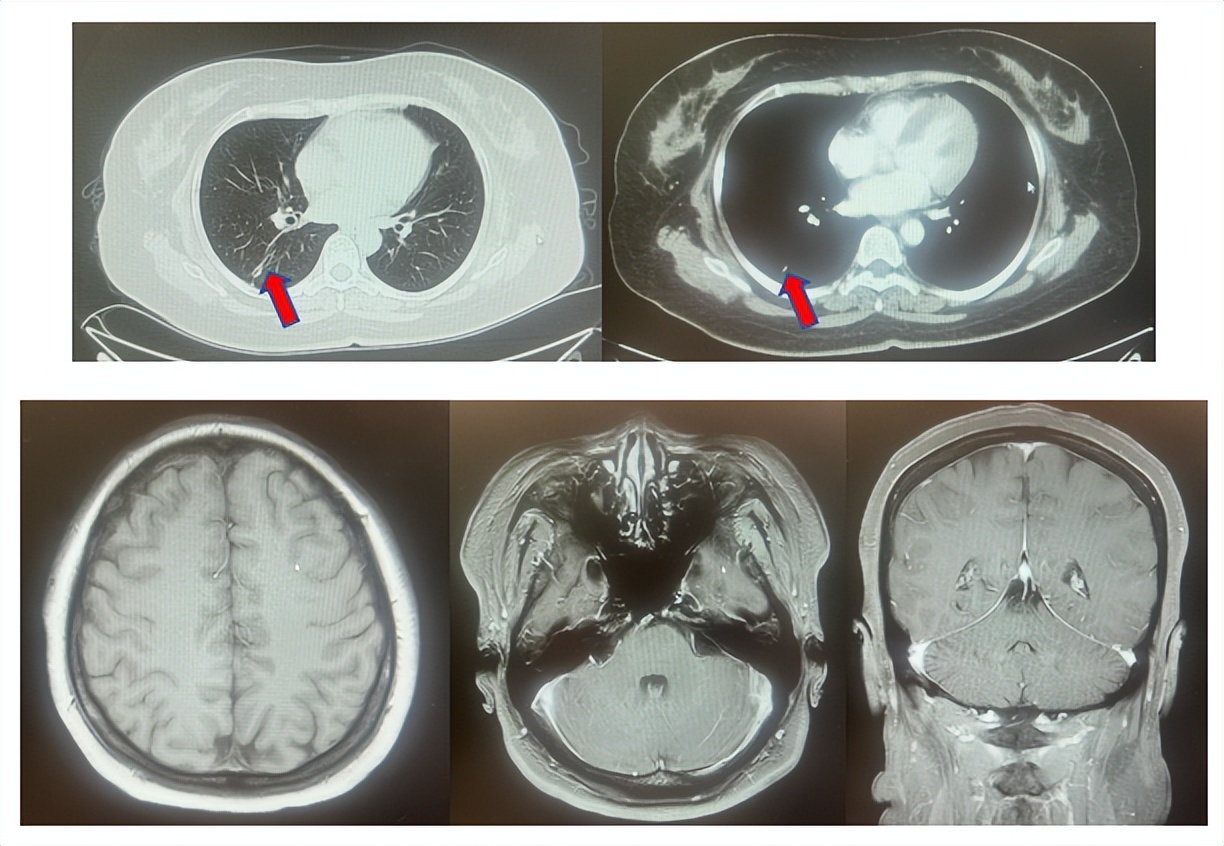

2.2影像学检查(图5)

肺+全腹CT增强:右肺中叶肿块,考虑恶性,双肺胸膜下炎症,双侧胸膜局限性增厚,右侧锁骨上淋巴结增大,纵隔淋巴结稍大;

颈部CT增强:右侧锁骨上及右颈部、纵隔多发淋巴结肿大。

脑MRI增强:头MR平扫+增强未见确切异常。

图5:上两图分别展示基线时肺CT肺窗及纵隔窗右肺中叶病灶影像,下两图表示基线状态时纵隔淋巴结及锁骨上淋巴结影像。

患者符合我科正在开展的一项“评估信迪利单抗或安慰剂联合培美曲塞和铂类化疗用于晚期或复发性肺鳞状细胞非小细胞肺癌一线治疗有效性和安全性的随机,双盲,III期研究(ORIENT-11)”临床研究入组条件,应用信迪利单抗或安慰剂联合培美曲塞+卡铂治疗4周期,信迪利单抗或安慰剂联合培美曲塞维持治疗13周期,后应用信迪利单抗或安慰剂应用至2年。试验结束后出组,揭盲患者为信迪利治疗组。治疗期间最佳疗效肺内病灶近CR(图6)。停药后每3个月-6个月复查随访,未见肿瘤复发转移征象(图6),截止至目前为止,一线无进展生存已超过75个月。

图6:上三图分别展示2019年6月患者达到最佳疗效时肺CT肺窗及纵隔窗右肺中叶病灶及锁骨上淋巴结影像,下两图表示2025年2月患者最近复查评效时肺CT肺窗及纵隔窗肺内病灶影像